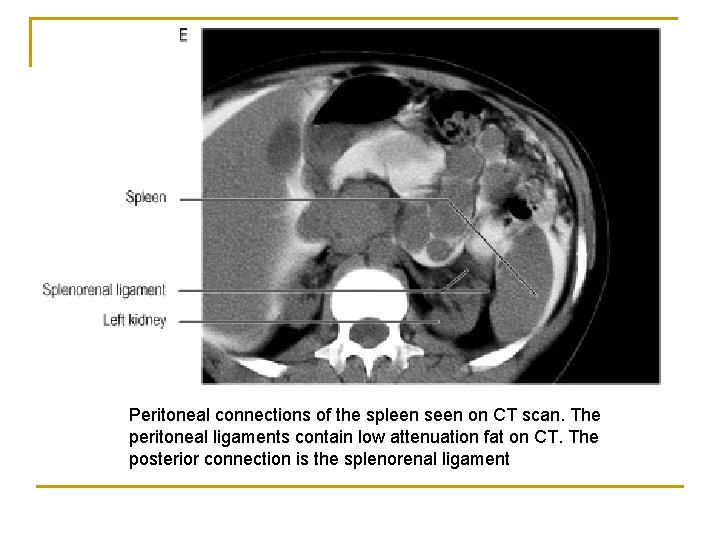

Peritoneal connections of the spleen seen on CT scan. The peritoneal ligaments contain low attenuation fat on CT. The posterior connection is the splenorenal ligament